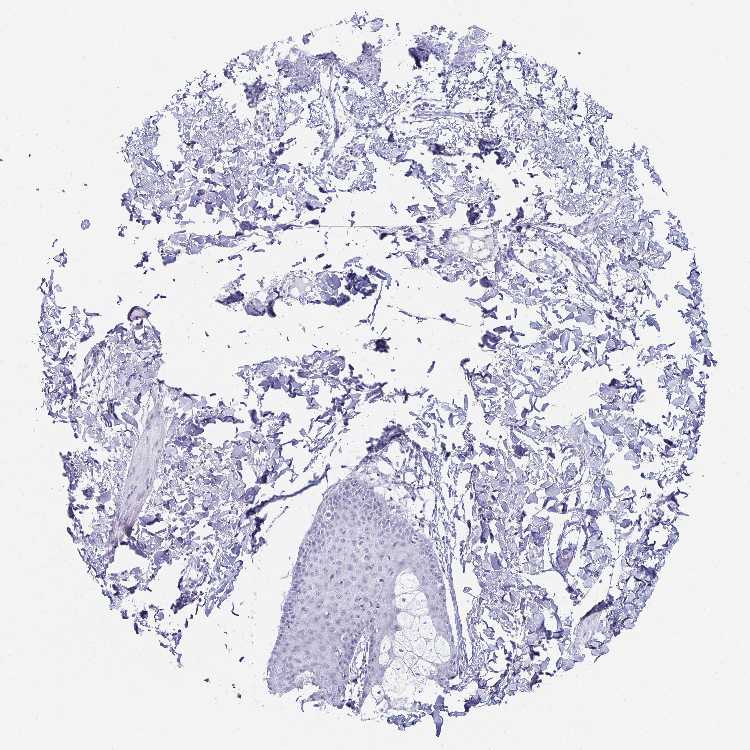

SKIN 1 - Antibody stainingi

Antibody staining in the annotated cell types in the current human tissue is reported as not detected, low, medium, or high, based on conventional immunohistochemistry profiling in selected tissues. This score is based on the combination of the staining intensity and fraction of stained cells.

Each image is clickable and will lead to virtual microscopy that enables deeper exploration of all samples and also displays staining intensity scores, fraction scores and subcellular localization as well as patient and tissue information for each sample.

Antibody HPA063655

Langerhans Not detected

Fibroblasts Not detected

Keratinocytes Not detected

Melanocytes Not detected